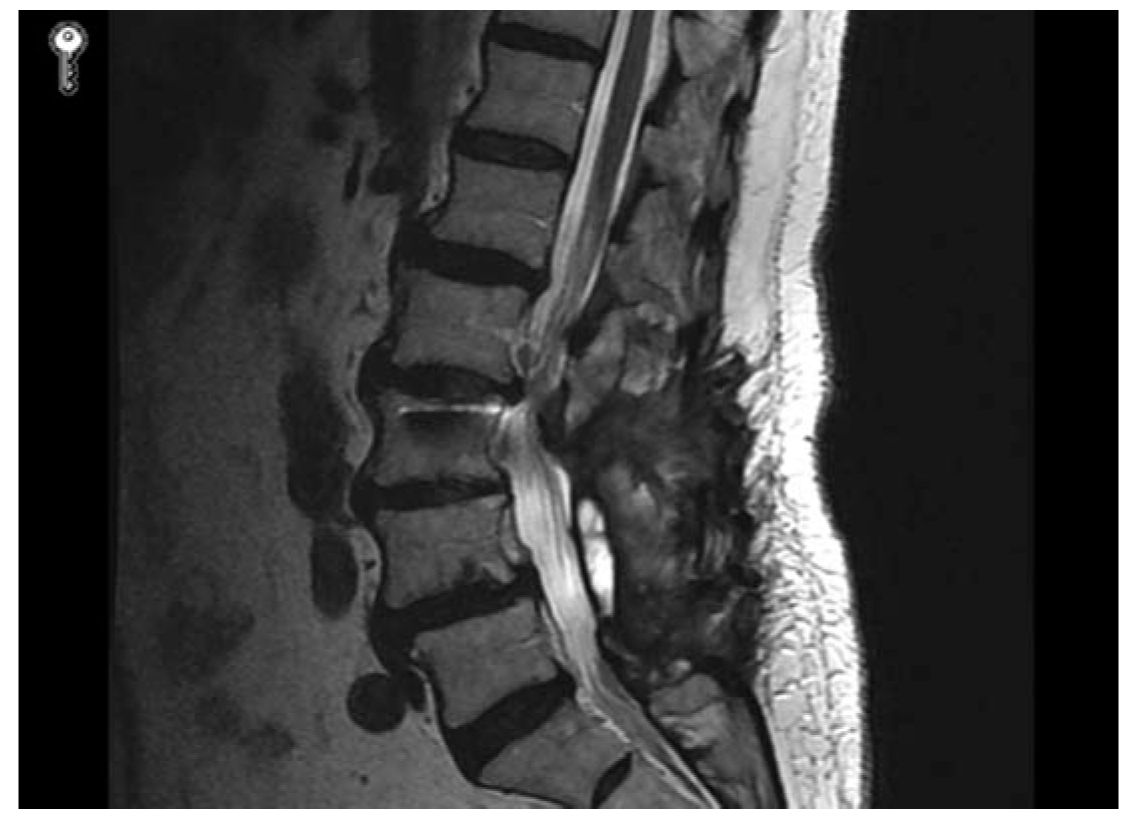

Approach to the Patient with Failed Back Syndrome Neupsy Key Round Back Syndrome This leads to a hunchback or slouching posture. a normal spine, when viewed from behind, appears straight. kyphosis of the spine, also known as hyperkyphosis or roundback, is a condition in which the upper back has an. In older people, kyphosis is often due to weakness in the spinal bones that causes. kyphosis is a condition in. Round Back Syndrome.